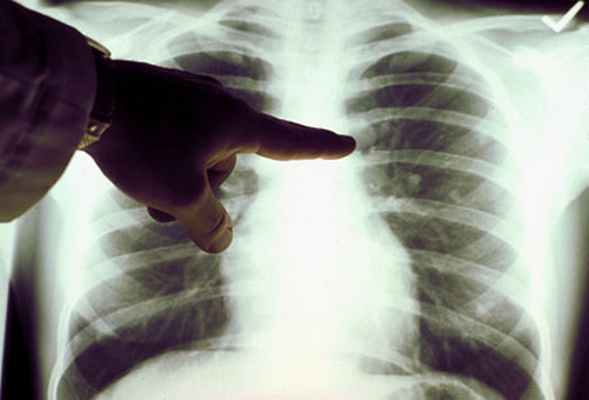

Усиление легочного рисунка в прикорневых зонах при эмфиземе

Эмфизема легких сопровождается повышенной воздушностью легочной ткани. Усиление прозрачности легких в верхних отделах при патологии на рентгеновском снимке сочетается с деформацией легочного рисунка в нижних легочных полях. Обогащение легочной ткани сосудами прослеживается при курении. Признаки эмфиземы и бронхита прослеживаются у 30% работников промышленных предприятий. Картина сопровождается деформацией, сгущением, усилением легочного рисунка. Клинические исследования показывают, что патологические изменения наблюдаются у мужчин после 40 лет. Основная сложность ранней диагностики эмфиземы – это усиление прозрачности легочных полей на рентгеновских снимках. Пневмосклероз в нижних отделах является компенсаторным состоянием. Формируется на фоне повышенной воздушности верхних легочных полей, нарушения проходимости воздуха по бронхиальному тракту. Рентгенограмма: пневмосклероз и фиброз у пациента с туберкулезом Когда эмфизема сочетается с признаками хронической дыхательной недостаточности, при расшифровке рентгенограмм врач-рентгенолог нередко описывает усиление бронхососудистого рисунка в прикорневых отделах с обеих сторон. Самостоятельно пациент не ощущает эмфизематозной болезни, при формировании дыхательной недостаточности возникает одышка. Дополнительным признаком хронической дыхательной недостаточности на рентгене считается «капельное сердце». При анализе снимка нужно обращать внимание на уплощение куполов диафрагмы. Функциональные пробы позволяют определить повышенную экскурсию диафрагмальных куполов с обеих сторон. Функциональные пробы позволяют выявить недостаточное поступление воздуха, увеличение размеров ретростернального пространства – признак Соколова. Данная клиническая картина характеризуется «капельным сердцем». Патология на рентгенограмме прослеживается обеднением легочных полей. Корни становятся нитевидными. Тени сосудов постепенно уменьшаются от центра к периферии за счет увеличенной воздушности легких. Обеднение рисунка прослеживается при эмфизематозных буллах, повышенной перфузии. Патологические изменения изучаются с помощью сцинтиграфии. При расшифровке рентгеновского снимка следует анализировать плотность легочной паренхимы на каждый квадратный сантиметр ткани. Дыхательную недостаточность нужно дифференцировать от признаков воспаления на рентгеновском снимке: • Плотные бронхиальные стенки; • Инфильтративные изменения бронхов; • Линейный ход сосудов; • Воспаление бронхиального дерева. При бронхите на рентгенограмме наблюдаются диффузные изменения рисунка – деформация, прикорневое усиление, потеря структурности корней, тяжистость рисунка. При хроническом бронхите формируются эндобронхиальные изменения катарально-гнойного или катарального характера. В заключение добавим, что анализировать легочной рисунок на рентгенограмме может рентгенолог с длительным практическим опытом, способный изучать самые мелкие детали рентгеновского снимка. Усиление и сгущение легочного рисунка с обеих сторон при хроническом брохите Усиление легочного рисунка в легочных полях при запущенном туберкулезе